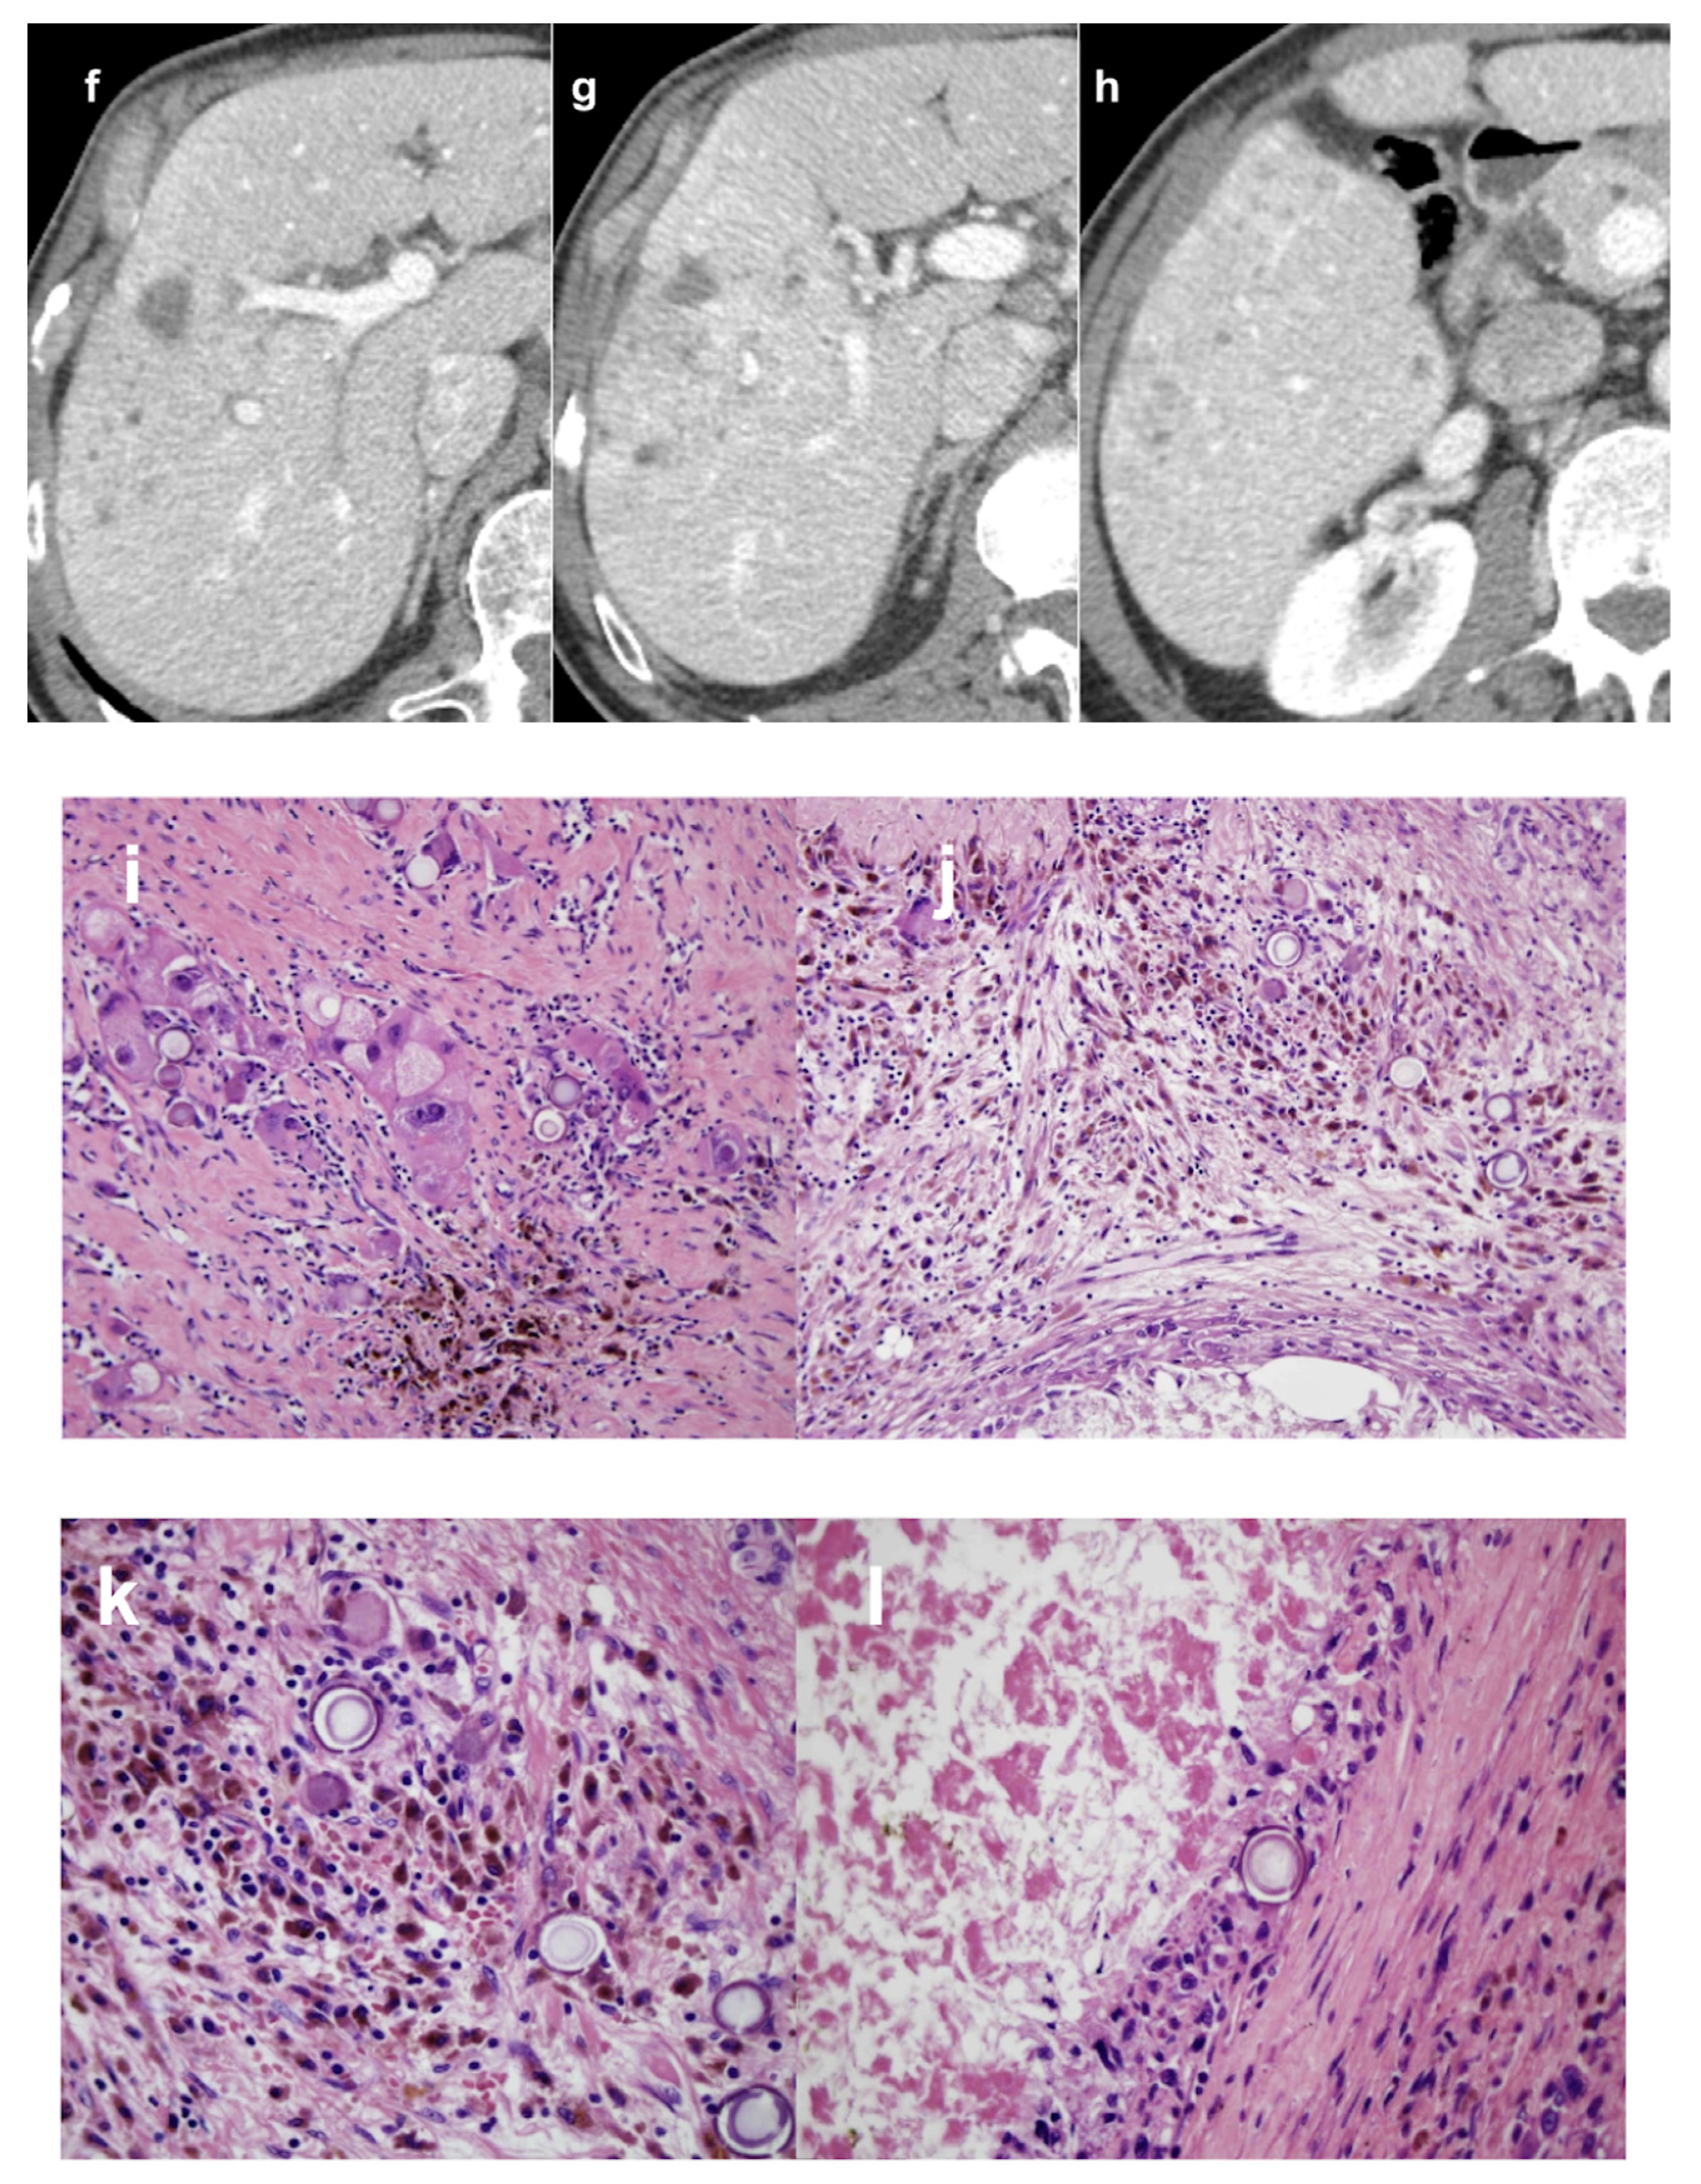

- Bauer, U.; Gerum, S.; Roeder, F.; Münch, S.; Combs, S.E.; Philipp, A.B.; De Toni, E.N.; Kirstein, M.M.; Vogel, A.; Mogler, C.; et al. High Rate of Complete Histopathological Response in Hepatocellular Carcinoma Patients after Combined Transarterial Chemoembolization and Stereotactic Body Radiation Therapy. World J. Gastroenterol. 2021, 27, 3630–3642. [Google Scholar] [CrossRef] [PubMed]